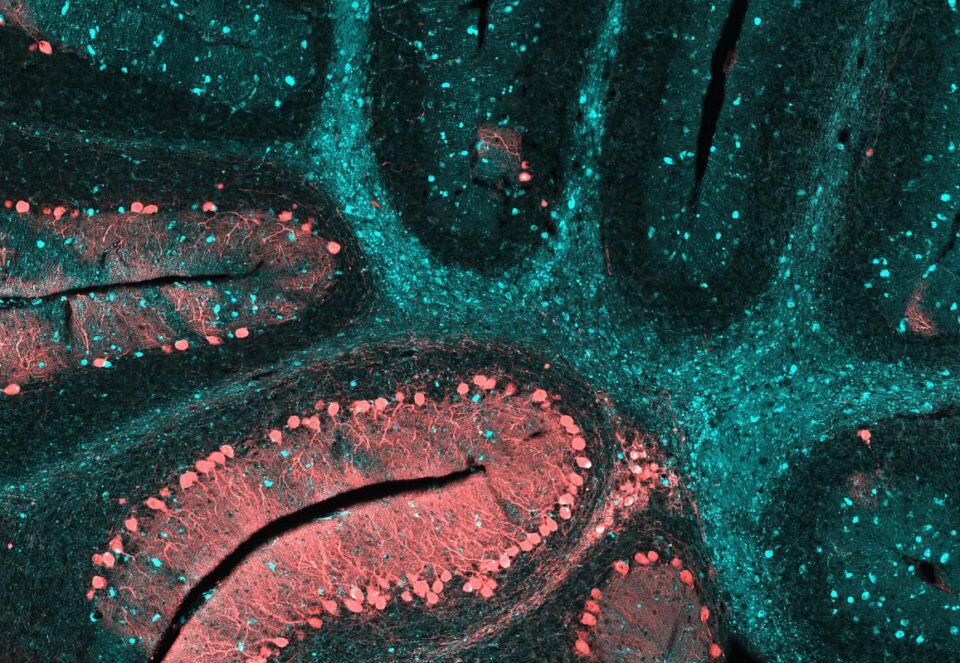

Мозжечок с признаками нейродегенеративной патологии, которая носит название болезни Ниманна-Пика. Здесь наблюдается тип C (NPC), причём, в конечной стадии заболевания. Это наследственный недуг, который имеет аутономно-рецессивный тип наследования и характеризуется накоплением в клетках липидов из-за нарушений липидного метаболизма. При типе С происходят мутации генов NPC1 или NPC2, которые отвечают за белок клеточной мембраны, транспортирующий холестерин и липиды внутрь клетки. Проявляется он как у маленьких детей, так и у взрослых, часто сопровождается задержками в развитии, повышенным мышечным тонусом, нарушением координации движений и некоторыми другими проявлениями. Бирюзовым цветом показаны плотные очаги скопления липидов в головном мозге. Учёные Национального центра по продвижению трансляционных исследований и Национального института детского здоровья и развития человека Юниса Кеннеди Шрайвера активно проводят исследования для того, чтобы усовершенствовать методы лечения NPC и д

Бирюзовым цветом показаны плотные очаги скопления липидов в головном мозге. Учёные Национального центра по продвижению трансляционных исследований и Национального института детского здоровья и развития человека Юниса Кеннеди Шрайвера активно проводят исследования для того, чтобы усовершенствовать методы лечения NPC и других лизосомальных патологий.